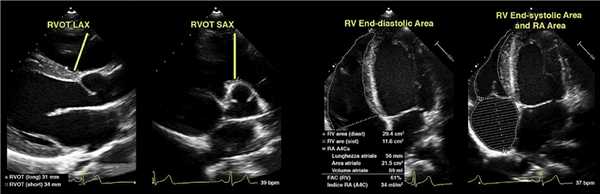

Оценка размера ПЖ и фракционного изменения площади (FAC).

От апикального 4-камерного окна, сфокусированного на ПЖ, следует провести контур от латерального кольца трикуспидального клапана вдоль свободной стенки до верхушки и обратно вдоль межжелудочковой перегородки до медиального кольца трикуспидального клапана.

Это должно быть выполнено в конце диастолы (левая панель), и область, проиндексированная по BSA, предоставит нам индексированную конечную диастолическую зону ПЖ.

Этот процесс можно повторить в конечной систоле (правая панель), из которого мы можем получить FAC следующим образом: FAC = (диастола RVA — систола RVA) / диастола RVA × 100%.

Оценка RVOT (RVOT1). Из окна PSAX и в конце диастолы измерение следует проводить от передней стенки аорты непосредственно до свободной стенки RVOT (на уровне аортального клапана). Представление PSAX более воспроизводимо, чем RVOT PLAX.